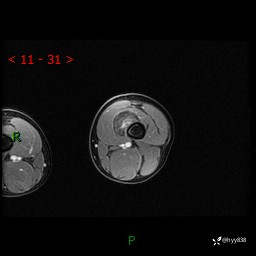

左大腿MRI平扫+增强